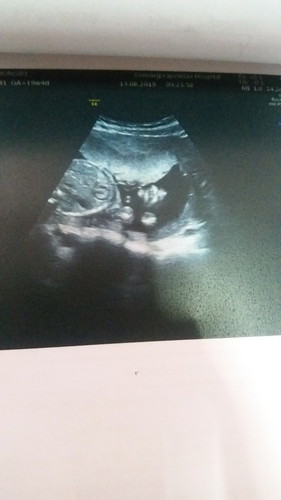

เพศลูก

แม่ๆช่วยดูหน่อยค่ะ เพศหญิงหรือชายค่ะ ท้องแรกดูไม่ออกค่ะ

อันนี้ภาพซาวด์ช่องท้องเด็ก ไม่เห็นเพศหรอกค่ะแม่

ครั้งหน้าซาวด์แม่ถามหมอนะคะ ว่าน้องเพศอะไร

แบบนี้ไม่เห็นหรอกค่ะ

ยังไม่เห็นเพศเลยค่ะ